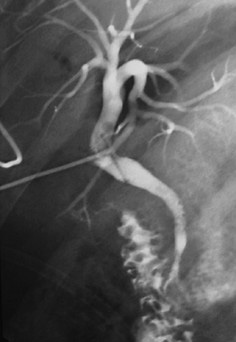

- Cholangiographie

peroperatoire et cholangiographie par drain de Kehr :

Comme le technique radiologique de cholangiographie per

cutanee , le produit de contrast doit injecte en

direct au canal choledocque per-operatoire ou

post operatoire par drain Kehr permet d'opacifier les

voies biliaires extra et intrahepatique permet de verifie

l'integrite des voies biliaire et la reste des calculs

inconnue

| |

Cholangiographie par drain de Kehr |

Images cholagiographies par

drain de Kehr . Les branches de voie biliaire sont

en vue |